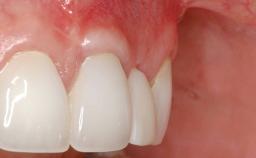

In this case, Shakeel Shahdad employs a two-layer matrix to repair a soft-tissue defect in a post-extraction healed site prior to implant placement with simultaneous guided bone regeneration. This approach resulted in a gain of keratinized peri-implant mucosa with optimal shade and texture. Soft-tissue defects are often encountered prior to implant placement and may result in deficient attached keratinized mucosa, which unless corrected will yield less than ideal esthetic outcomes. The presence of keratinized mucosa has been proposed as one of the prognostic factors for the survival of dental implants (Adell and coworkers 1986) with reported greater reductions in gingival and plaque indices after increasing the width of keratinized mucosa by soft-tissue augmentation (Giannobile and coworkers 2018; Thoma and coworkers 2018).